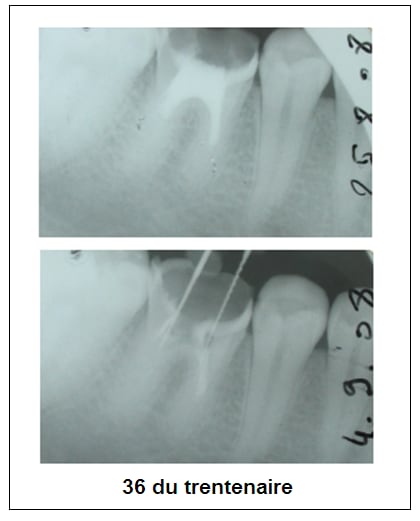

Je viens d'en récupérer une sur une 36 chez un nouveau patient de 30 ans, pan lingual cassé cet été, canaux totalement calcifiés, j'arrive pas à passer, aucune lumière (je sais je n'en suis pas une non plus hélas...). Que faire?

sur la 36 du trentenaire,j'arrêterais tout avant les faux canaux:de plus il ne semble pas y avoir de pb apicaux?

2-La 36 du trentenaire va très bien au niveau apical. J'ai besoin des canaux pour la reconstituer, je vais donc me contenter d'enlever le ciment à base d'eugénate... au risque de me voir reprocher de ne pas avoir boucher les racines "correctement". Je trouvais juste bizarre qu'il n'y ait plus de canaux, au delà de ce que j'ai appelé une pulpo ancienne (basse j'en conviens).